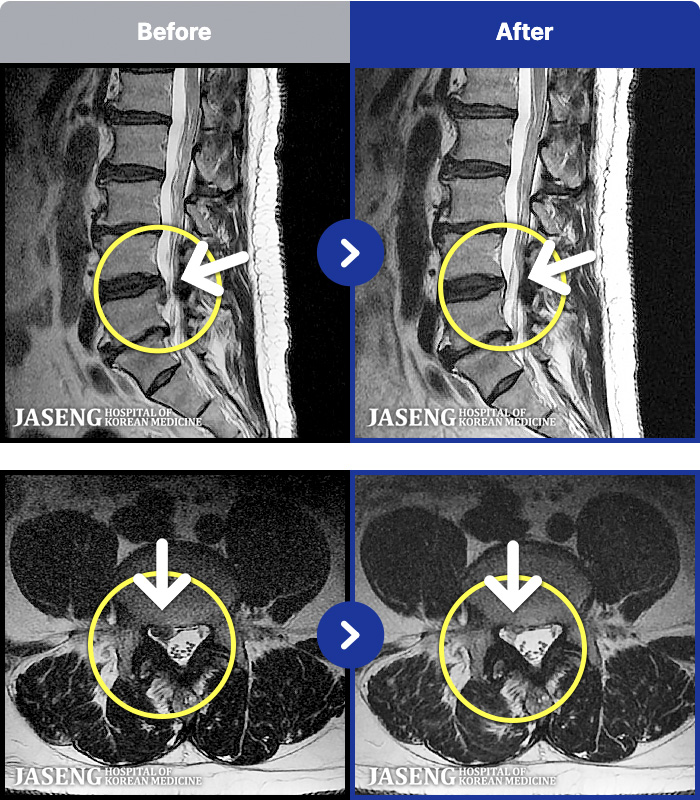

[Կñ:25.03.29~25.07.17]

[_㸮ũ] 㸮

No.52

ȸ 36

2026.01.06